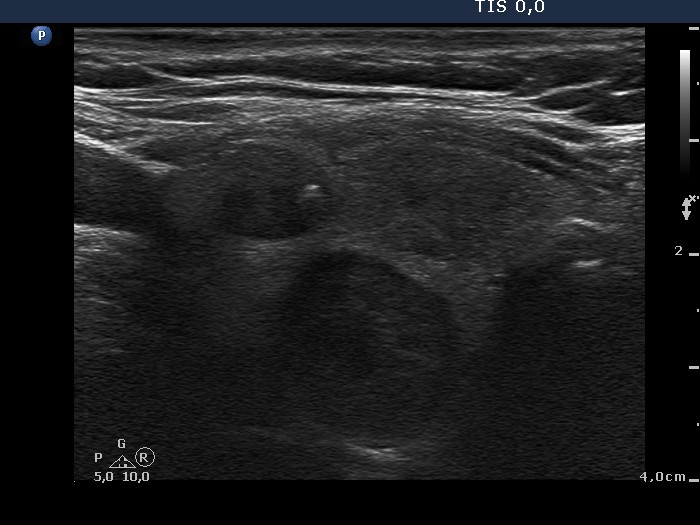

First examination (1st and 2nd rows of images)

Clinical presentation: a 47-year-old woman was referred for evaluation of a multinodular goiter detected on screening. She had no complaints.

Palpation: the right lobe was nodular.

Functional state: euthyroidism with subnormal TSH (TSH 0.18 mIU/L, FT4 18.3 pM/L).

Ultrasonography: the right thyroid contained three nodules, the two ventral lesions were minimally-moderately hypoechogenic, while the dorsal one was hypoechogenic. The latter presented a combined type 2 and type 3 vascular pattern.

Cytology was performed from the dorsal, hypoechogenic nodule and resulted in benign, follicular proliferation. The risk of a carcinoma was estimated to be less than 1%.

Scintigraphy was performed which disclosed increased uptake in the right lobe. The individual nodules could not be identified.

We advised regular follow-up.